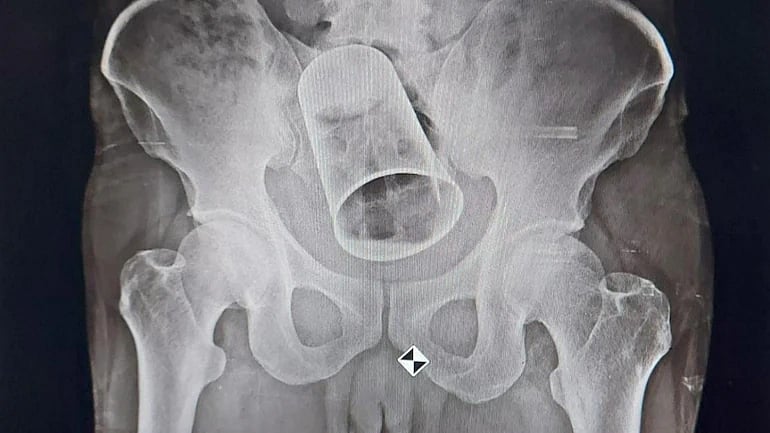

In Odisha, a group of doctors removed a steel glass that had been placed into a man's colon by his friends.

The man had a steel glass surgically removed from his colon on Sunday at MKCG Medical College and Hospital in Berhampur. The man's companion placed the glass inside his anus while he was inebriated.

On getting the x-ray results, the doctors realised that he had a glass stuck in his rectum.

First, the doctors made an attempt to remove the glass through the rectum. But after failing in these attempts, they suggested Rout get surgery.

Performing the procedure were a team of medical professionals led by associate professor Sanjit Kumar Nayak, doctors Subrat Baral, Satyaswarup, and Pratibha, as well as professor Charan Panda, head of the hospital's surgical department. To get the steel glass, they sliced into the gut.